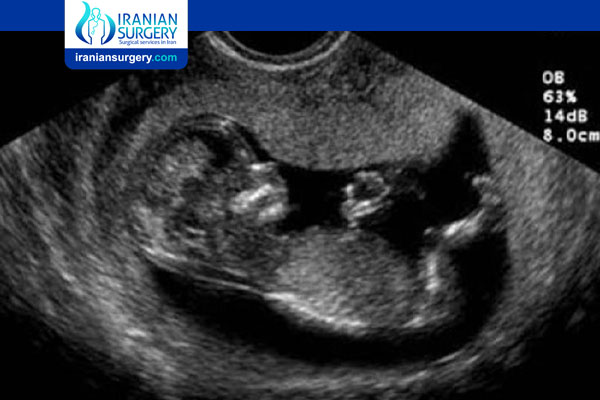

توجد حاليًا طريقتان شائعتان لتحديد نوع الجنين، الأولى تسمى التلقيح الصناعي (IVF) والثانية أسلوب الحياة. في التلقيح الصناعي، بعد إجراء الاستشارات والفحوصات اللازمة يتم أخذ 12 إلى 17 بويضة من الأم وعدد من الحيوانات المنوية من الأب خلال شهر، يتطلب هذا الأمر حقن الهرمونات في جسم الأم، ولها بعض الآثار الجانبية، مثل: